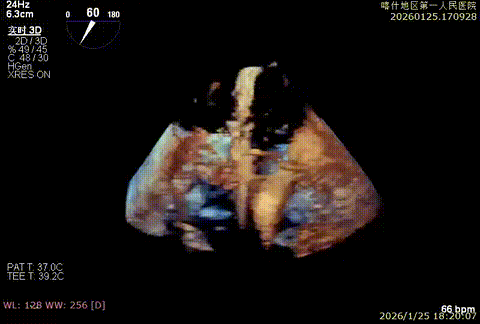

3D enface脱垂情况

X-plan 反流情况

3D enface组织桥稳定

3D enface组织桥

3D enface 组织桥稳定

3D enface 反流少量

该例患者为DMR,1,2,3区均见脱垂,主要脱垂位于1区及外交界后叶脱垂,病变解剖结构亦相对复杂。术前制定手术策略:使用3把XTR解决患者瓣叶脱垂与二尖瓣反流。术中首先进行房间隔穿刺,最终穿刺高度4.5cm。穿刺成功后将SGC和XTR-CDS依次送入左心房,通过操控“M”旋钮调节SGC,使二尖瓣夹避开华法林脊并成功定位于2区正上方。在2区进行弹道测试成功后,进行Orientation调整。最终在1区将二尖瓣夹送入左心室,成功捕捞和夹持瓣叶后缓慢关紧夹。第二枚XTR植入2区,采用双拉链技术,从两个夹子中间植入第三枚夹子,固定脱垂区域降低反流。TEE检查见二尖瓣反流程度降低至少量,二尖瓣双孔组织桥稳定,肺静脉逆流改善明显,手术安全结束。